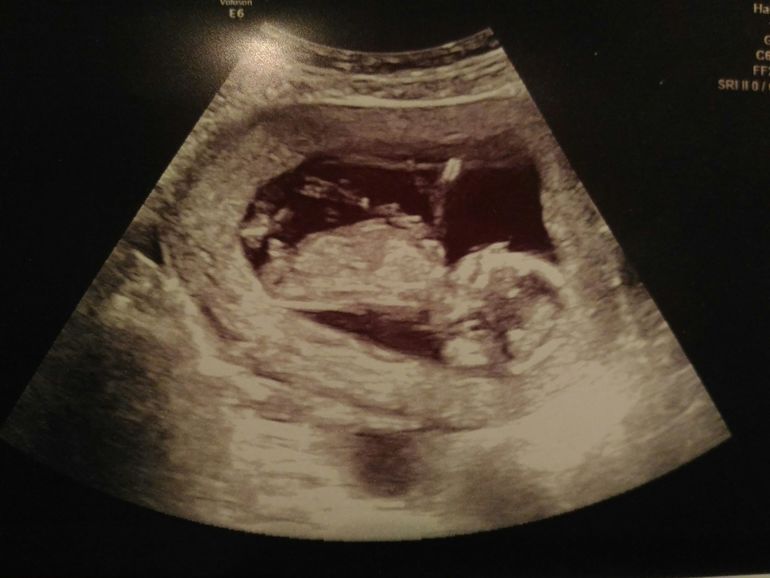

13 недель и первый скрининг

Всё о нашей беременностиСходила на первый скрининг.

Растет наша ягодка, уже 68 мм.

Как обычно крутился, вертелся, ногами и руками упирался в стенки плаценты.

Уже был виден желудочек крохотный, сердечко во всю бьется, пальчики на ногах и ручках.

Акушерка сделала все замеры: носик, шея... И сказала, что опережает в развитии на 1 день )))))))))